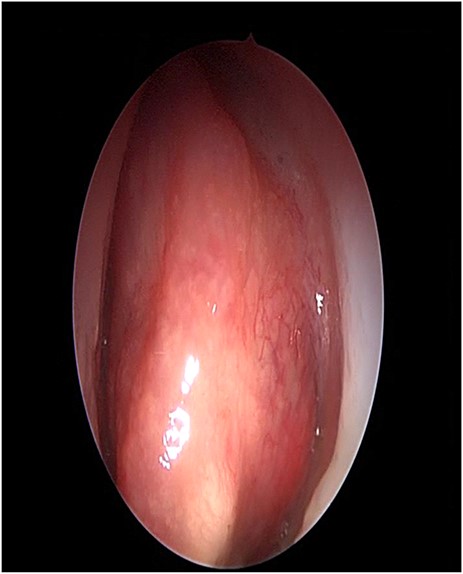

The patient underwent image-guided endoscopic endo-nasal removal (Fig. 5) of a large fibro-osseous tumor, the tumor was adherent to the orbit and skull base which was removed (Fig. 6). The resected tumor was sent to the histopathological examination, which confirmed the final diagnosis of fibrous dysplasia. The patient remained free of symptoms with no recurrence for 3 years after the resection.

Endoscopic image showing the cavity after tumor removal from the orbit and skull base.